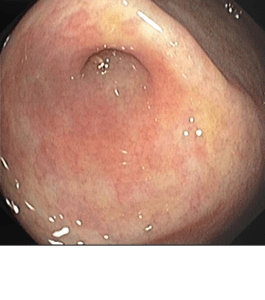

Polipectomía

La polipectomía es un procedimiento endoscópico que se utiliza para extraer pólipos en diversas partes del tracto gastrointestinal, como el esófago, estómago, duodeno o colon....